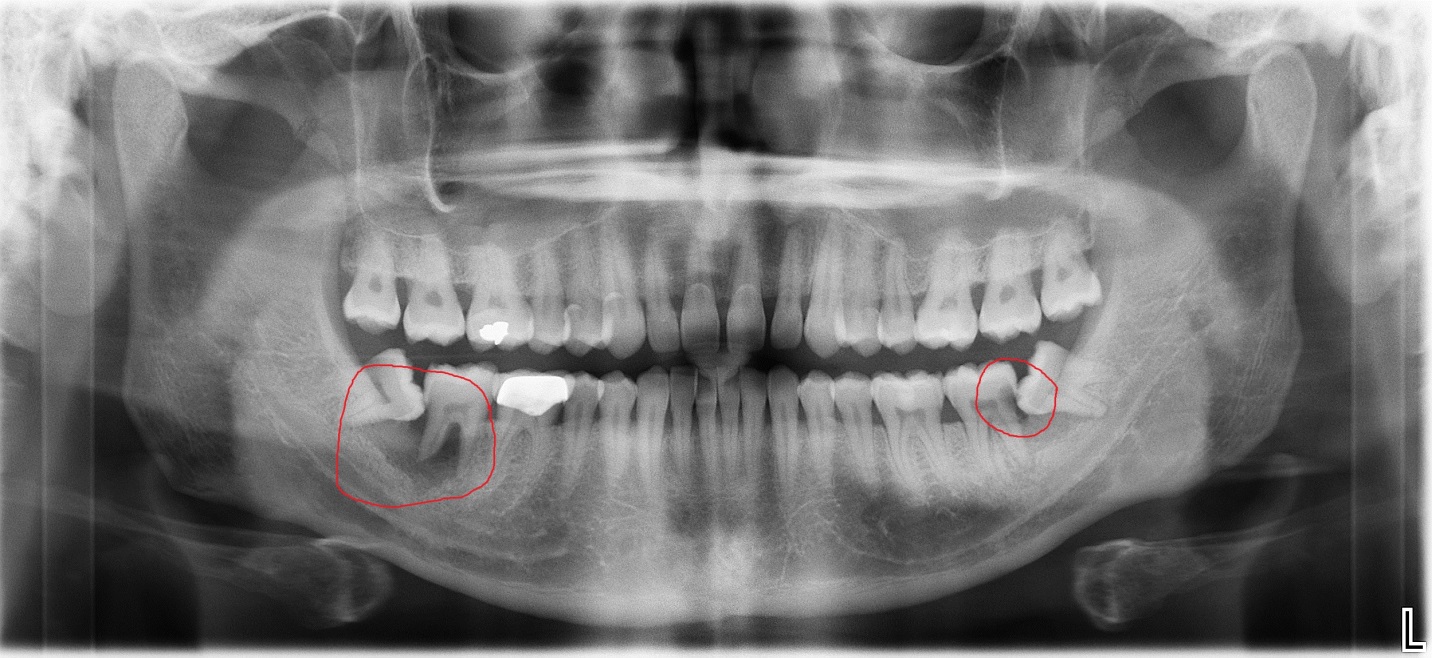

How can I tell if my wisdom tooth is impacted?

Is an X-ray necessary before wisdom tooth extraction?